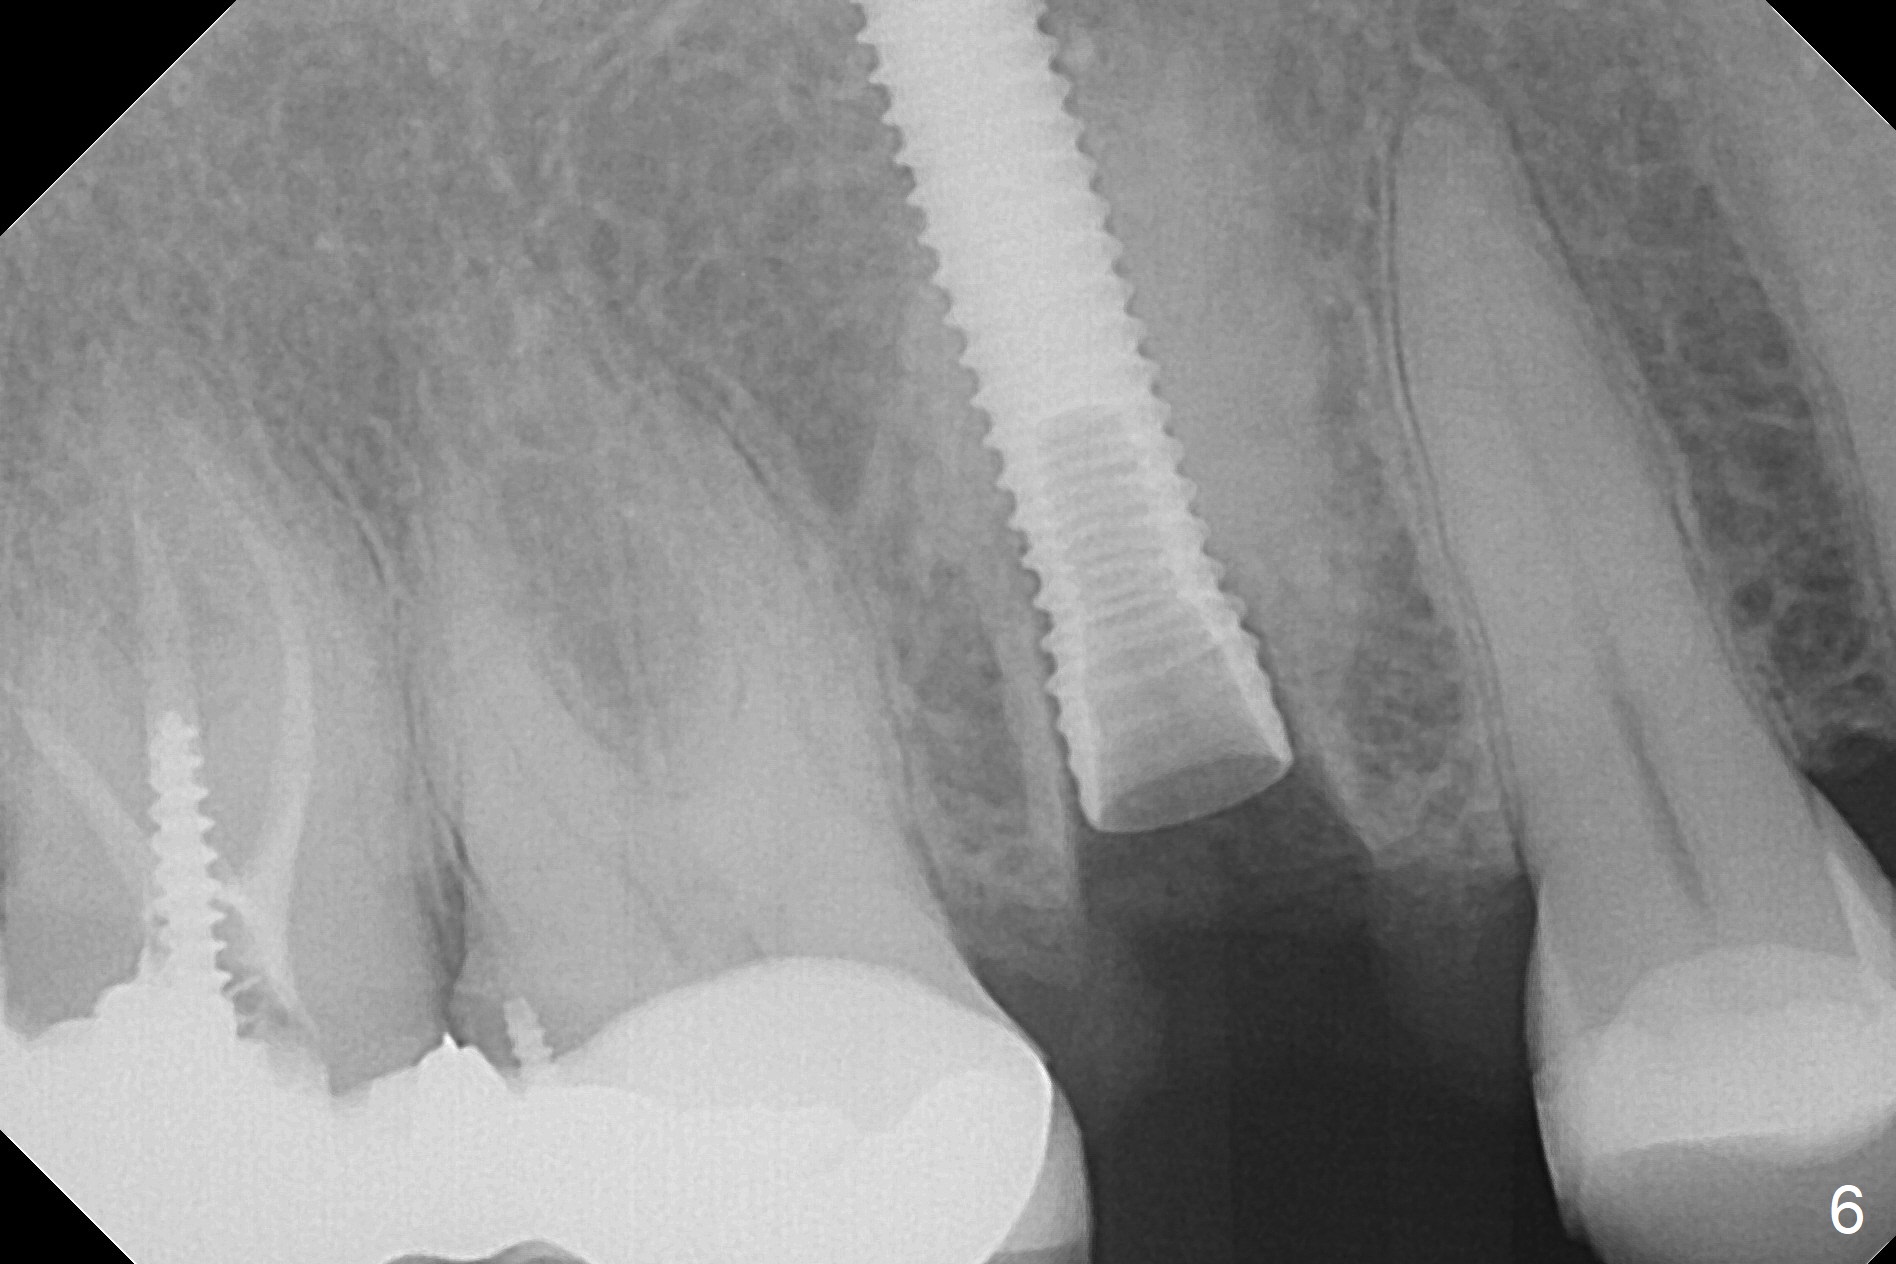

After extraction of the tooth #4 with palatally subgingival fracture (Fig.1 ^), white hard tissue is found in the socket, the density of which is hard (Fig.2 D). When osteotomy passes this portion of the bone (Fig.3 red dashed line), bone density feels reduced suddenly. The osteotomy is moved mesially slightly (Fig.4 (2.7 mm drill)). When a 3.8x15 mm dummy implant is placed with stability, there is an apical space (Fig.5 red dashed line). Therefore the final implant is longer (3.8x18 mm, <30 Ncm, Fig.6, 7). Vanilla graft is placed around the implant and a 4.5x4(4) mm abutment is placed immediately for an immediate provisional (Fig.8). Although the provisional easily dislodges in spite of remake, the implant seems osteointegrated with decreased space 4 months postop (Fig.9). The gingiva is healthy, although it covers the abutment margin partially. Gingivectomy appears necessary for impression.